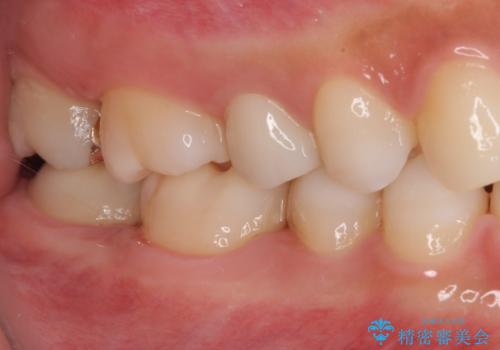

- 近々海外へ転居するとのことで、事前に処置をしておくべきむし歯がないか、気にして来院された患者様です。

レントゲン写真などから、速やかに処置を行うべき歯が2歯あったため、それぞれセラミックインレーとPGAインレー(ゴールドインレー)にて修復治療を行うこととしました。

どちらの歯も痛みなどの症状はなく、治療後も異常所見なく経過をたどっています。

上顎大臼歯は向かい合った人から見えることはほとんどないため、切削量が少なく、適合の良いゴールドインレーが大変おすすめとなります。